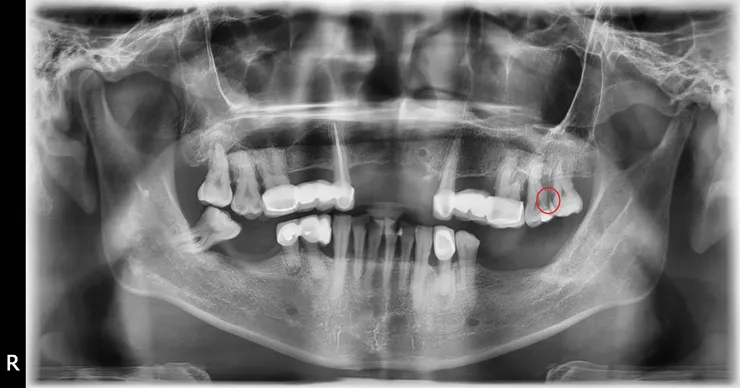

病人後來終於拔掉#28,可內可直接看到我之前在X光片看到的蛀牙,照給他看,他才相信